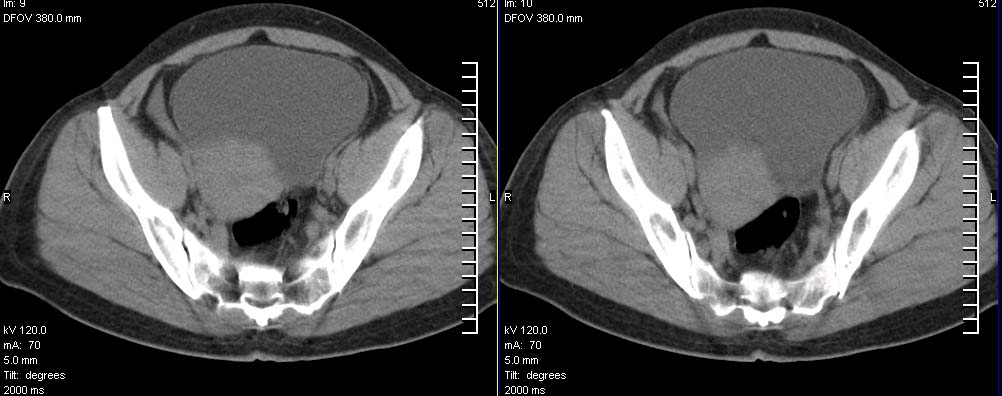

标题: CT9722:卵巢巨大占位,约10*18*21CM大小

卵巢巨大占位,约10*18*21cm大小

考虑右侧附件来源肿瘤--囊腺瘤可能性大,子宫增大,建议增强扫描.

右侧附件区巨大囊性肿块,边缘光滑,密度较高,左侧缘由多个低密度区,首先考虑囊腺瘤可能。